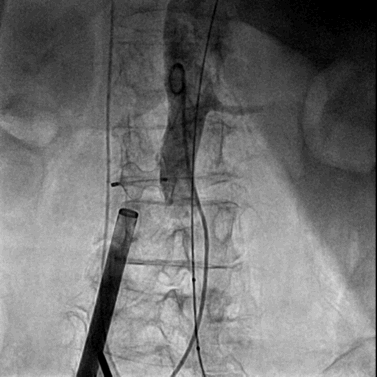

将0.014英寸导丝交换为超硬导丝后,置入22F大鞘达腹主动脉内。

经右侧股静脉沿超硬导丝置入22F大鞘达腹主动脉内